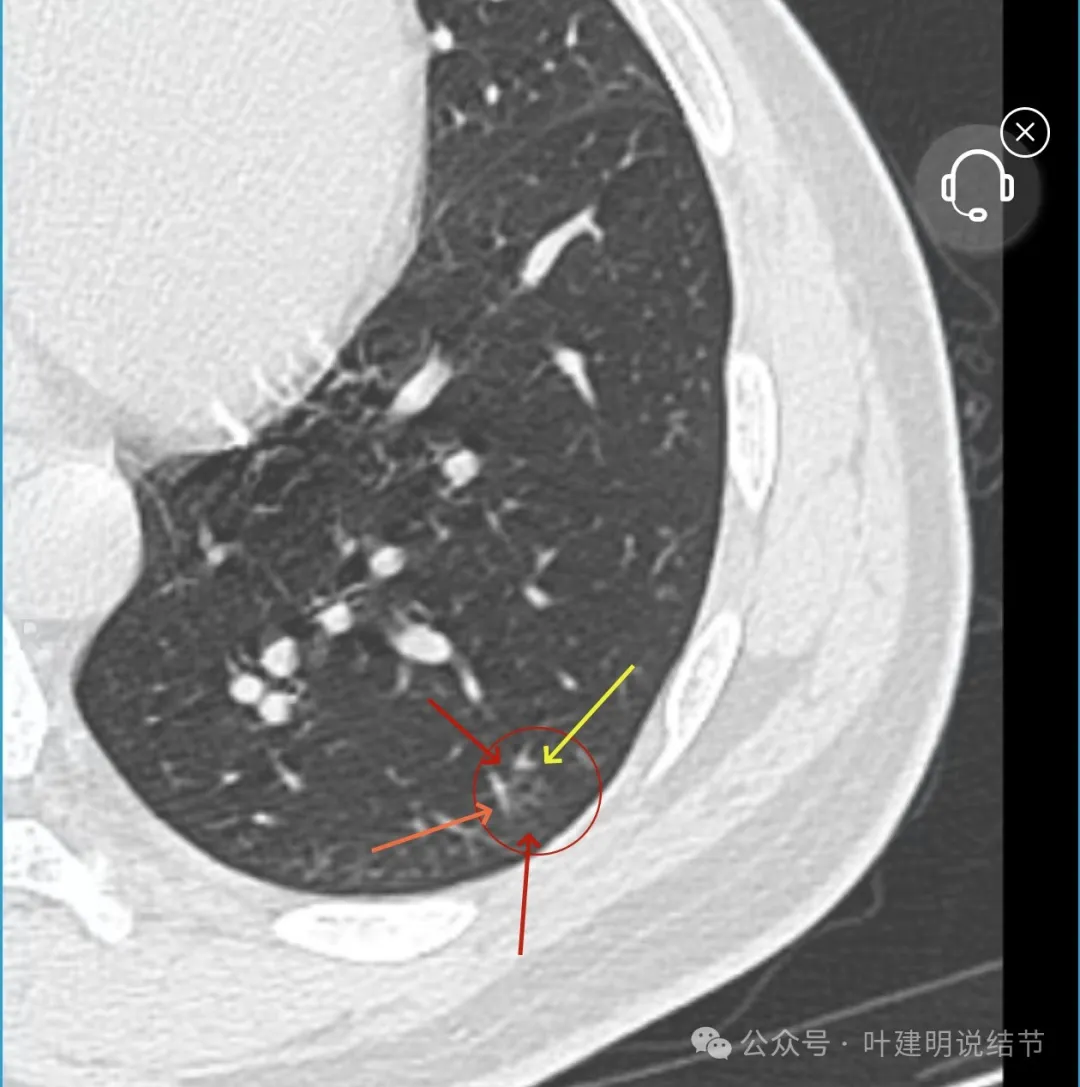

左下叶结节,轮廓稍显模糊,邻近有血管走行,无血管弯征,病灶中间密度稍低,结节密度很淡,仅小片状模糊影似的。

当地说考虑微浸润性腺癌的左下主病灶影像连续层面展示:

病灶出现,显模糊。

上图层面轮廓较清,但密度很淡,似见血管走行,但靠左前方的似条状磨玻璃密度与血管连着的到底是血管分支还是结节的一部分,其实并不确切。如果其实是血管分支,那病灶与它之间就不是空泡。

病灶在此层整体边缘显糊,灶内有空泡似的,瘤肺边界欠清。

边缘不平,还是灶内多发小空泡?邻近血管与之紧贴,但血管无异常走行。病灶密度很低,显糊。

中间所谓空泡更像是细支气管扩张,内壁非常光滑且圆形。

病灶边缘区淡而模糊。

这个病灶会是微浸润性腺癌吗?当然没有病理诊断,我也不能说百分之百必不会,但这样的病灶已经风险大到必得尽快手术切除干预了吗?显然还早着呢:1、影像不是典型的结节状;2、边缘与轮廓模糊不清;3、灶内似有细支气管扩张(更容易是细支气管扩张伴少许周围炎或肺泡上皮增生);4、血管邻近走但无牵拉影响;5、没有实性成分,没有锐利毛刺,没有胸膜牵拉,没有血管进入,没有任何倾向风险性高的影像特点。我一直强调:肺结节是否要干预处理,不要纠结于最后病理是什么,而要看风险高低;而风险高低的最重要术前判断依据一是随访有无进展,二是有没有实性成分。只要没有肉眼可见的影像上的实性成分,风险就是低的!何况病理也是人看的,原位还是微浸润,不典型增生还是原位有时也在一念之间。